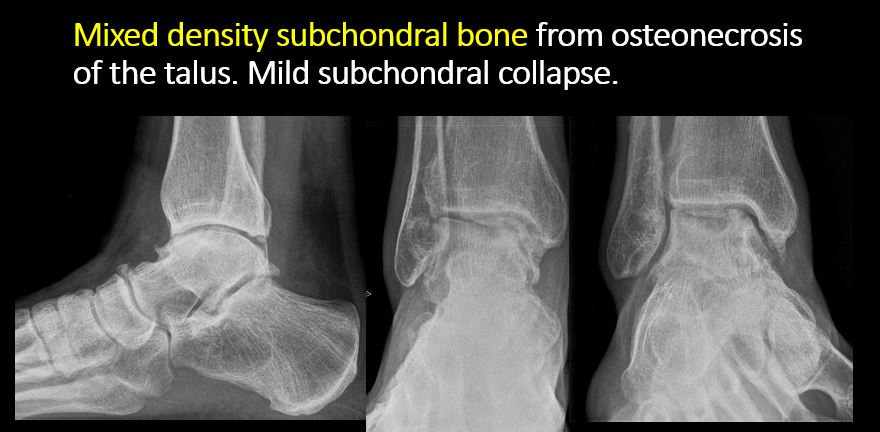

There is linear or irregular lucency, or increased density, cortical depression, flattening, or collapse with or without cortical disruption or thickening, which may be from a compression or impaction fracture, stress or insufficiency fracture, osteonecrosis, or other fracture. |

Yes | NA |

There is subchondral abnormality (lucencies, increased density, erosion) with or without cortical disruption or thickening which may be from osteonecrosis, osteochondritis dissecans, osteochondral fracture, inflammation, infection, or other abnormality. |

No | NA |

There is increased, decreased, or mixed density in subchondral bone. |